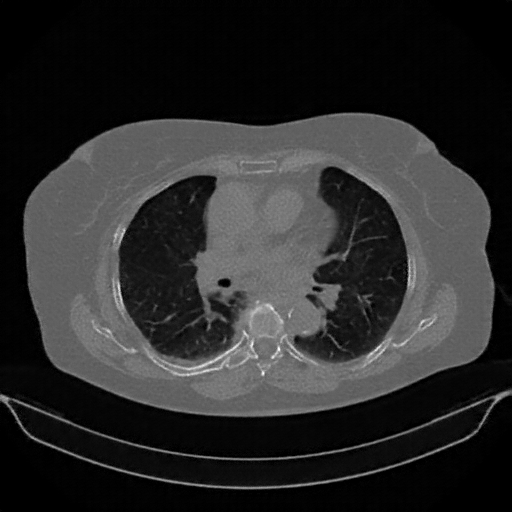

Original NATIVE CT scan (input)

Mediastinum window (WL 40, WW 400 β†’ Low βˆ’160, High +240)

Actual HU range: [-160.0, 240.0]